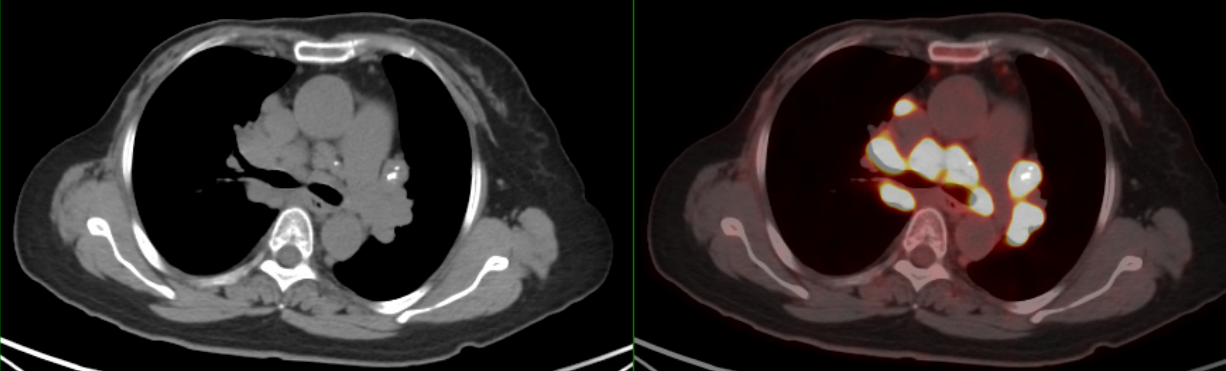

PET/CT示:雙側(cè)鎖骨上、縱隔、胸骨后、雙肺門、雙側(cè)肋骨旁、腹腔、腹膜后、盆腔及左側(cè)腹股溝見多枚代謝異常增高淋巴結(jié),較大者約3.4×2.1cm,SUVmax約20.7。

PET/CT診斷:考慮結(jié)節(jié)病,建議病理檢查。

18F-FDG PET/CT在腫瘤患者的全身評估中具有顯著優(yōu)勢,在乳腺癌術(shù)后出現(xiàn)縱隔和肺門腫大淋巴結(jié)時,不但能顯示淋巴結(jié)全身的分布特征,且能更早發(fā)現(xiàn)胸外病變及隱匿性病變,同時體現(xiàn)不同部位淋巴結(jié)的FDG攝取程度,判定病灶活動性,有利于結(jié)節(jié)病與乳腺癌術(shù)后復(fù)發(fā)或淋巴瘤等的鑒別診斷。由于結(jié)節(jié)病的診斷主要依靠組織病理學(xué)活檢,PET/CT可以提示適合的活檢部位,提高活檢診斷成功率。

此例患者由于乳腺癌的病史,臨床初步懷疑轉(zhuǎn)移。PET/CT顯示縱隔、肺門淋巴結(jié)腫大,且呈對稱性分布,密度均勻,邊界清晰,無明顯融合,F(xiàn)DG高攝?。淮送饪梢姸喟l(fā)腹盆部,頸部淋巴結(jié)次之,分布較散,體積及FDG攝取小于縱隔和肺門淋巴結(jié),也不是乳腺癌術(shù)后易轉(zhuǎn)移的部位。綜上考慮符合結(jié)節(jié)病表現(xiàn),最終得到病理證實,患者因此避免了不必要的抗腫瘤治療。